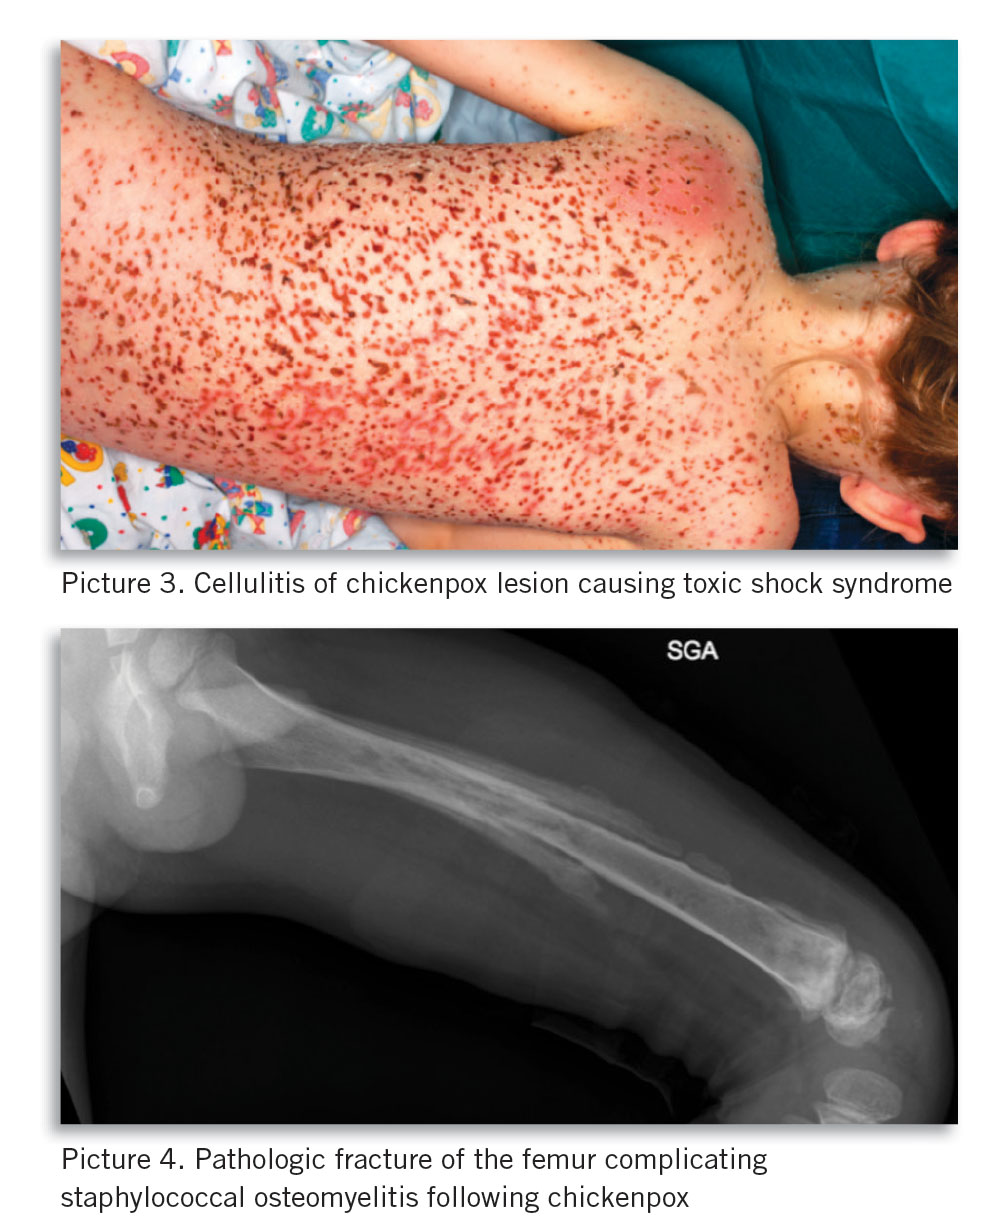

Bacterial super-infection (see Picture 4) complicating chickenpox should be suspected in any child with fever that persists or recurs beyond four to five days of illness, where severity of pain is disproportionate, or with redness and swelling around skin lesions.